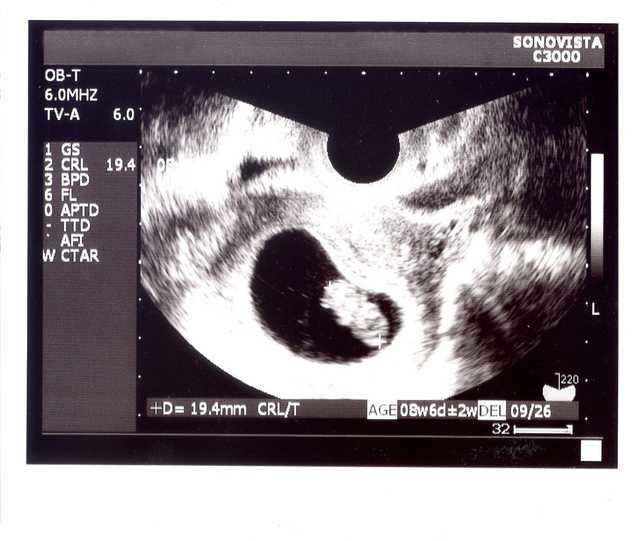

妊娠8週目の赤ちゃんの身体の大きさは13~18ミリ程度で、重さは1~3g程度というのが一般的な数値です。

軟骨は骨に、超音波検査では頭と胴体の二頭身の姿が見られる

器官の発育に関しては、妊娠6週頃に形成され始めた軟骨が徐々に固くしっかりとした骨へと変化を遂げます。

口や目などのパーツも、唇やあご、まぶたなどの段々と細かい部分までつくられていきます。超音波検査でも、頭と胴体が分かれた二頭身の姿がはっきり見られるようになるでしょう。

検査の時に見る角度にもよりますが、手足も少し出ているのが確認できることもあり、段々人間らしい形になっていくのが分かります。